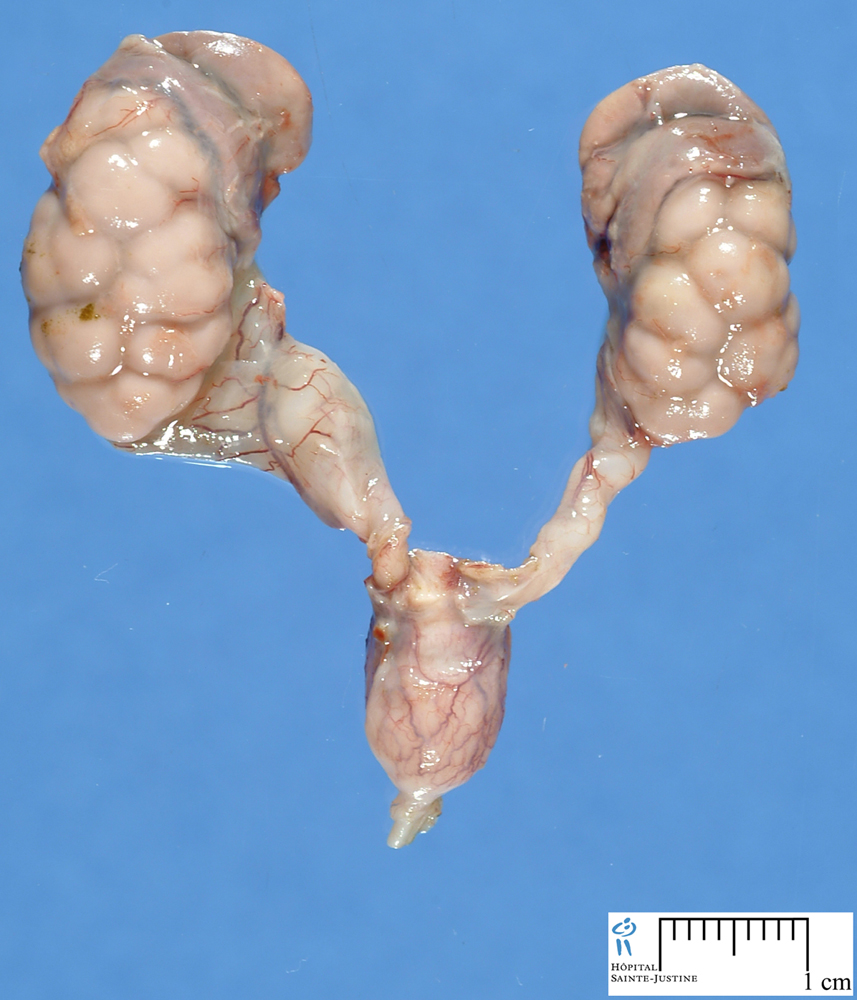

هیدرونفروز شرایطی است که قسمتی از کلیه که ادرار را جمع آوری میکند بیش از گنجایش خود ادرار دارد که منجر به تورم و اتساع کلیه می شود. هیدرونفروز می تواند در یک یا هر دو کلیه اتفاق بیفتد.

بعضی از جنین ها برای مدت کوتاهی دچار تورم کلیه ها می شوند و سپس برطرف می شود. اگر هیدرونفروز جنینی رفع نشد می تواند به علت مشکل جدی در سیستم ادراری همانند انسداد مجاری ادراری یا ریفلاکس ادراری باشد.

درمان هیدرونفروز در نوزاد تازه متولد شده بسته به تعداد کلیه های درگیر و شدت درگیری می باشد.